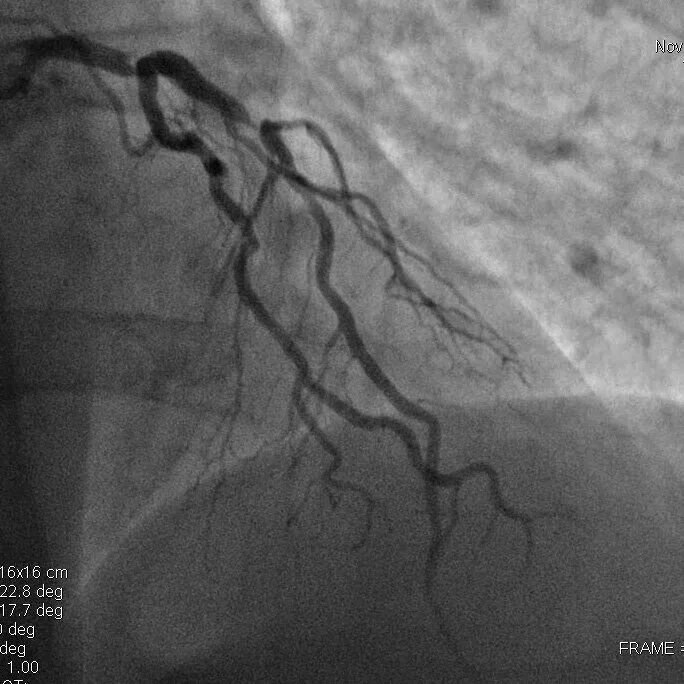

Повторный инфаркт после стентирования